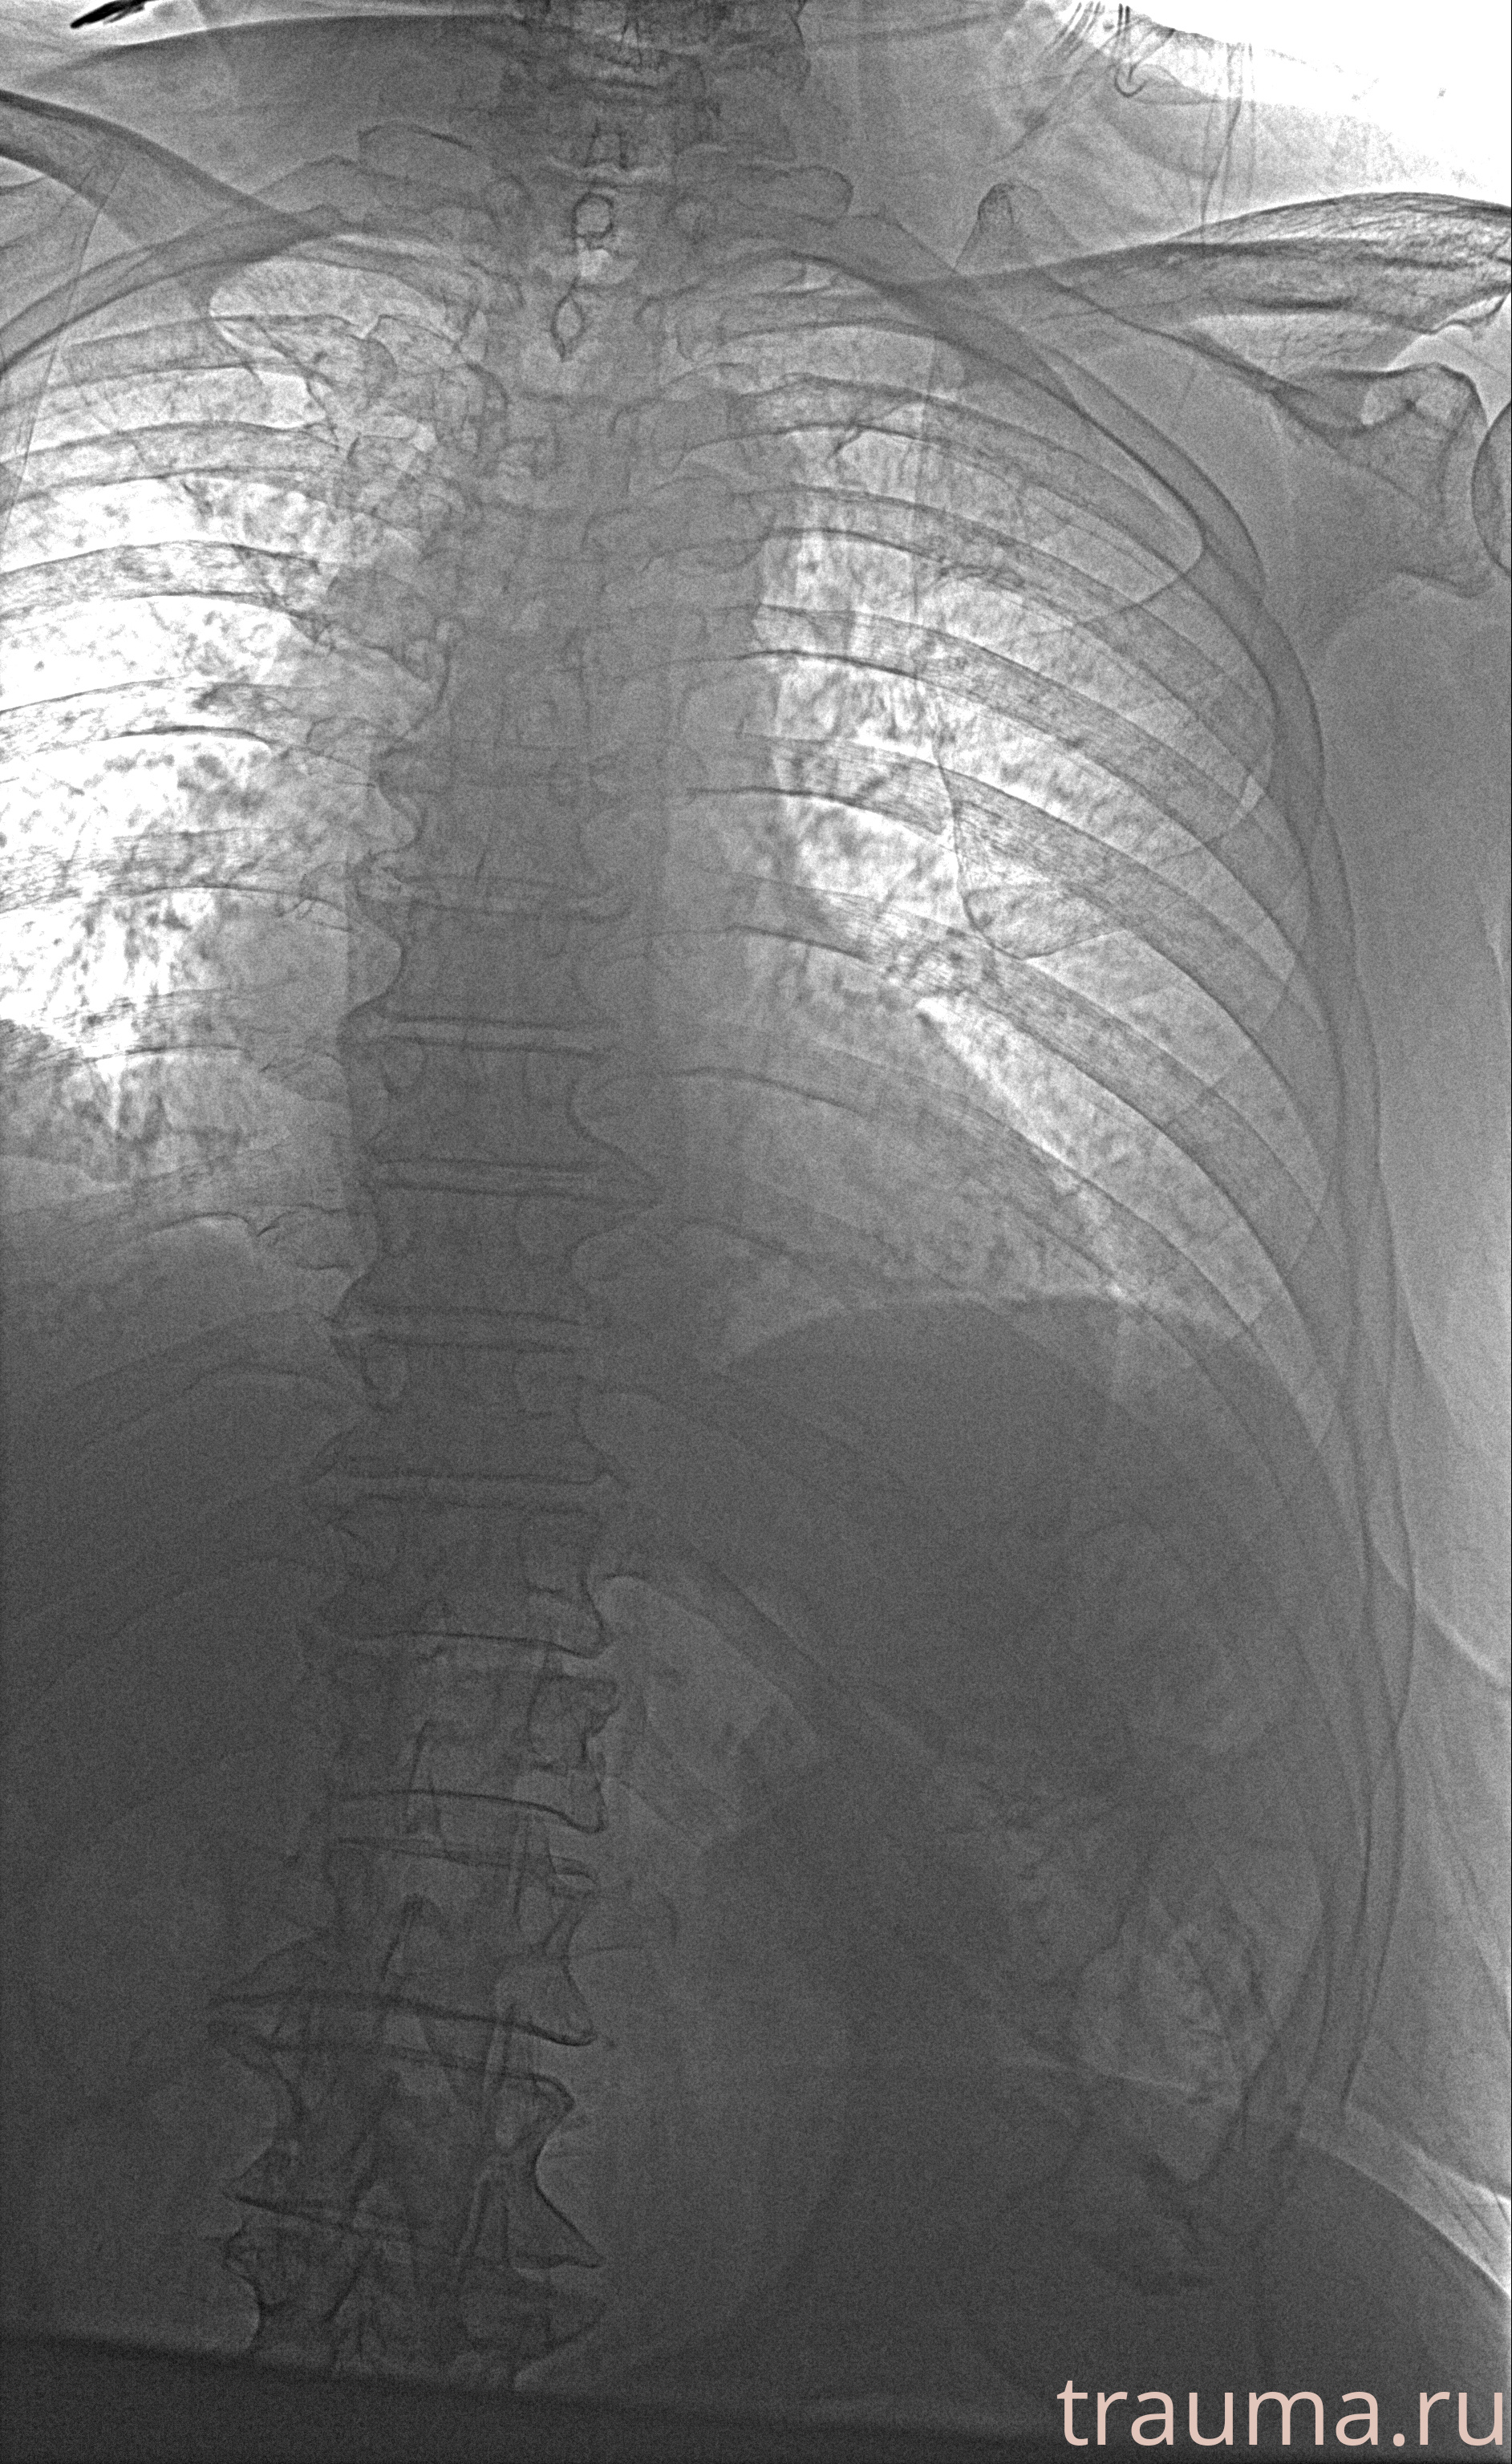

Рентгенограммы

Рентген на дому: по вашему адресу приезжает врач-рентгенолог, травматолог-ортопед с мобильным рентгеновским аппаратом, проводит диагностику травмы или заболевания, делает необходимые рентгенограммы, дает рекомендации по дальнейшему лечению. Получить качественные снимки в домашних условиях возможно благодаря уникальной методике, разработанной МосРентген Центром для института  Склифосовского

при переломе шейки бедра и пневмонии от компании МосРентген Центр - партнера Института имени Склифосовского